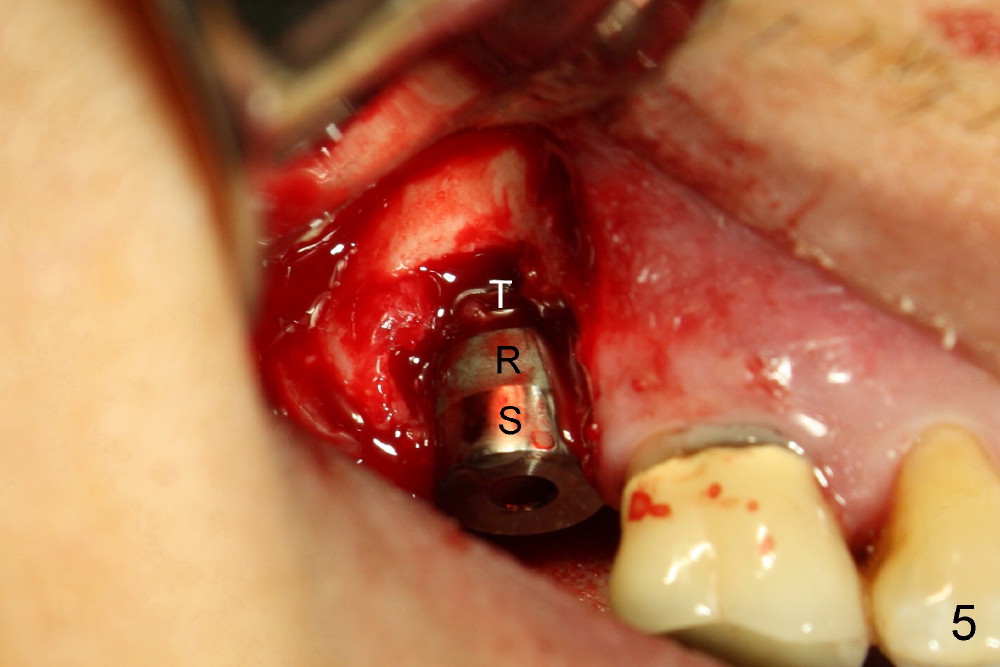

The 60-year-old man is a bruxer. All of the three upper right molars are nonsalvageable (Fig.1). Since #2 is symptomatic, it is planned to be extracted and restored first. As expected, there is severe alveolar destruction (single large socket), while the base bone is solid. A series of tapered osteotomes (2-5 mm) are used to create osteotomy in the base bone (gaining 4 mm into new bone), followed by 4.5x20 mm tap at the depth of 17 mm from the gingival margin (Fig.2). Then the depth is adjusted to 14 mm; the bone expansion and osteotomy continue until using 7 mm tap with good binding to the bone (Fig.3). A 7x14 mm implant is placed with insertion torque more than 60 Ncm (Fig.4). No bone graft is used for sinus lift considering sinus membrane perforation. The buccal flap is raised to reveal bony defect, which is covered by Osteogen (a synthetic bone graft) and then collagen membrane (Fig.6 *). Five days postop, the membrane undergoes a type of transformation (Fig.7 *) leading to a gingival tissue (Fig.8 *, 18 days postop). By 3 months, the gingiva has normal appearance (Fig.9), while the implant seems to be osteointegrated (Fig.10). Once the infected source is removed, our body has potential to regenerate.

The patient complains food impaction between #1 and 2, six months post cementation. The former has mobility II. Although there is keratinized gingiva buccal to these sites (Fig.12), there is no papilla buccally (Fig.13) or palatally (Fig.14). The palatal pockets between #1 and 2 are deep with tenderness. X-ray shows bone loss between the sites (Fig.11 white *); the periodontal explorer can be felt to touch the distal implant threads (<). Extraction and immediate implant are recommended for #1. Twelve months later, the patient agrees with the treatment plan. The tooth #3 needs extraction and immediate implant, 2.5 years after the one at #2.

Periimplantitis develops with bone loss 4 years 5 months post cementation (Fig.15). It appears that the implant should be removed (Fig.16, unipost cemented with Ketac, prepare special screw driver after handpiece making a slot), followed by bone graft (Fig.17 red circles), particularly mesial to #1 implant and PRF. Prepare Titanium brush to clean the exposed implant threads of #1 implant. When the defect heals (with increased bone height, Fig.18 greyish area), place a smaller implant (green) with guide.